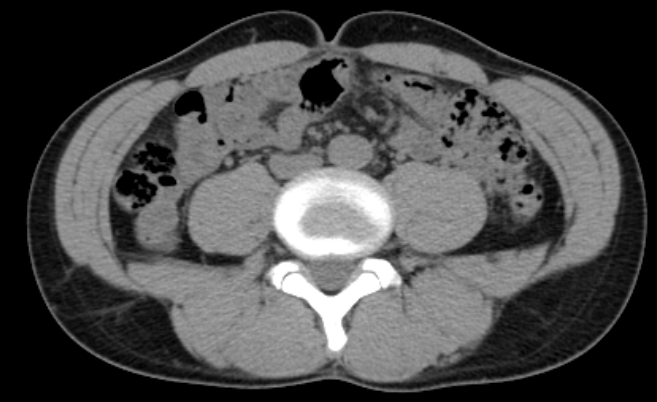

先日、健診でCTを撮ったので2018年 (このときはステロイド漬けで55.8kg、体脂肪率12.0%、筋肉量46.5kg、胴囲74-75cmあった!) と比べてみました。

2018/3/9 皮下脂肪 前12mm、後ろ 32mm

黒いところが脂肪。筋肉の外が皮下脂肪で、内側が内蔵脂肪。

ヘソは凹んでいるし、脇腹後ろにお肉たっぷり。